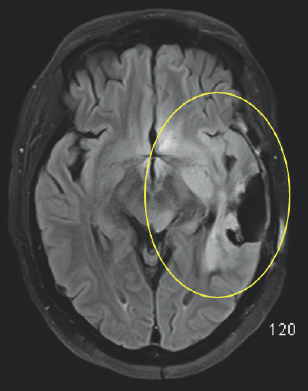

Unfortunately, an MRI scan in October of 2019 revealed worrisome imaging of potential local progression of the tumor (Fig. 2.1–2.3). In addition to this troubling discovery, abnormalities in Columbus’s neuro-cognitive capacity, such as issues with his memory and word-finding capabilities, were gradually becoming more pronounced. This word-finding difficulty showcased itself through his inability to retrieve words for use in regular speech, despite his retention of the ability to understand the English language. To treat these new symptoms, Columbus was put on the steroid dexamethasone.

FIGURE 2.1 Brain MRI before surgery. Axial (left) and coronal (right) post-contrast images show a large mass that appears bright after being injected with IV contrast within the posterior and anterior aspect of the left temporal lobe (yellow arrows and circle), most consistent with high-grade glioma.

FIGURE 2.2 Brain MRI before surgery. Additional nodular areas of abnormal enhancement that appear bright after being injected with IV contrast are noted in the anterior temporal lobe (yellow circle) and the left aspect of the midbrain (red circle). There is surrounding signal alteration on the MRI sequence image most consistent with swelling (yellow oval).